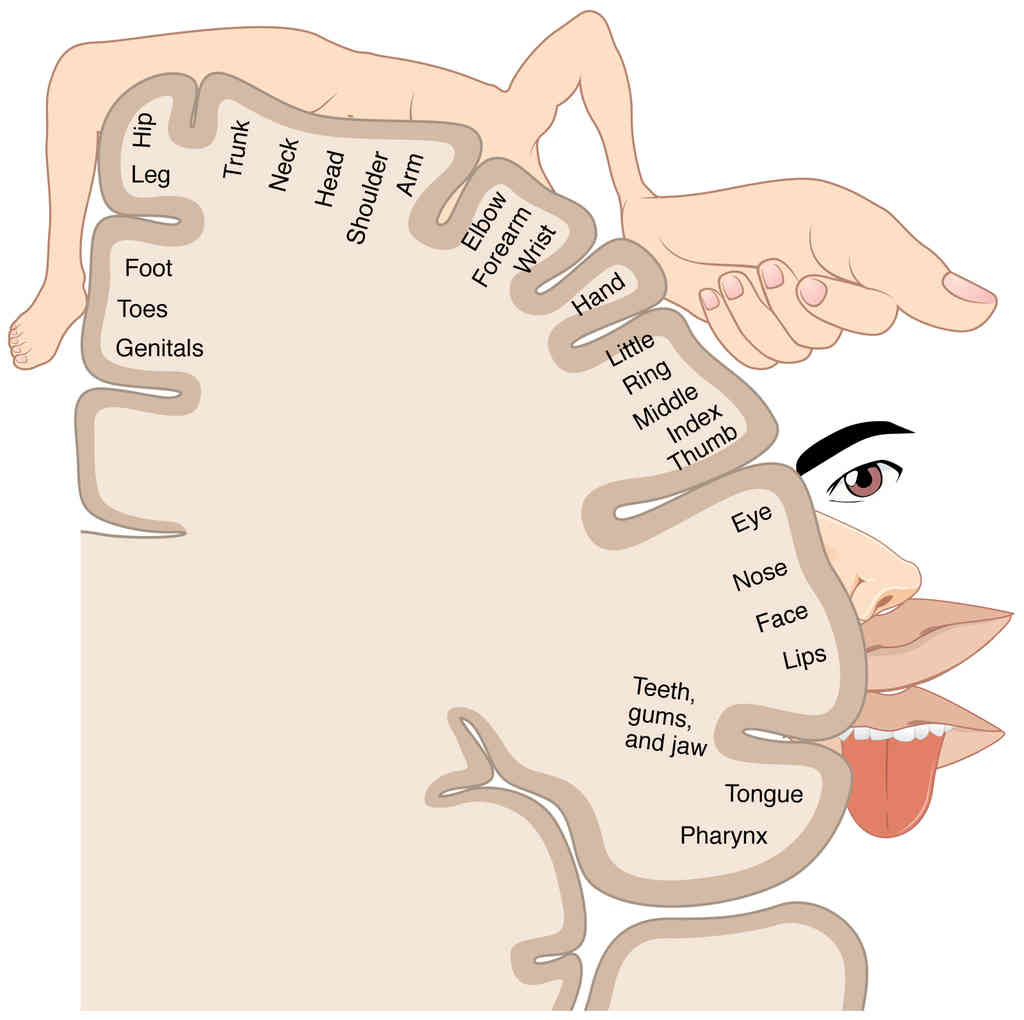

This page is under construction. For now, it is just a resource of the images found in the OpenStax Anatomy and Physiology Handbook. It wil slowly change into a revision tool. Each slide has a number. Use this to refer to the slide. When completed, it will have an unlabelled section, with labelled slides in parallel. On the unlabelled slides, write your answer and use the labelled slide to assess yourself. Keep track by also noting the number on each slide. Improvement at each attempt is important, more so than full marks on a first attempt.